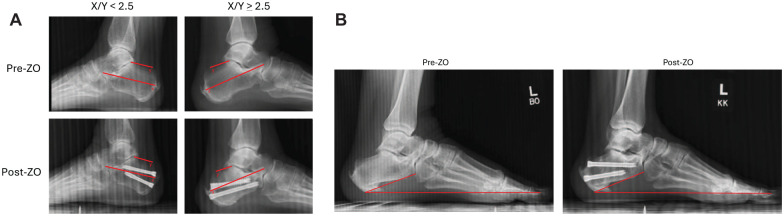

Background: The percutaneous dorsal closing wedge calcaneal Zadek osteotomy (ZO) is an effective treatment for patients with insertional Achilles tendinopathy (IAT), although consensus is lacking on ideal patient selection. Tourné et al proposed that a preoperative calcaneal X/Y ratio <2.5 defines surgical candidacy, but this criterion remains controversial. This study evaluated whether patients with IAT benefit from percutaneous ZO regardless of preoperative X/Y ratio.

Methods: A retrospective comparative study of 27 patients undergoing percutaneous ZO was performed. Patients were stratified into 2 cohorts based on preoperative X/Y ratio (<2.5 vs ≥2.5). Primary outcomes were PROMIS scores for pain, function, and mobility at 3, 6, and 12 months. Secondary outcomes included complication rates and radiographic parameters. Minimal clinically important differences were used to assess clinical significance.

Results: Between May 2022 and May 2024, 27 cases were included in the current analyses. Seventeen cases had an X/Y <2.5; 10 had an X/Y ≥2.5. Both cohorts demonstrated significant improvement in PROMIS pain, function, mobility scores (P < .05). Patients with X/Y ≥2.5 demonstrated statistically greater improvement in pain scores than patients with X/Y <2.5 (P = .049) at 1-year follow-up. Ninety-eight percent of patients were satisfied following ZO intervention.

Conclusion: Percutaneous ZO demonstrated meaningful improvement in patients' function, pain, and mobility regardless of preoperative X/Y ratio. These findings challenge the use of the <2.5 X/Y threshold as a strict selection criterion. Percutaneous ZO may be a viable option for a broader population of IAT patients than previously considered.